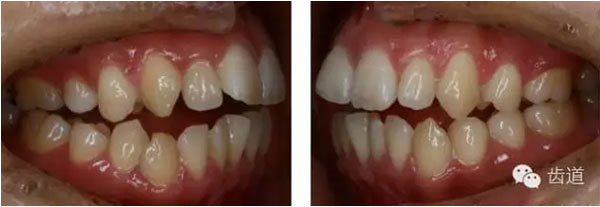

治療前后口內(nèi)相對(duì)比

矢狀向、垂直向及開(kāi)合:上頜磨牙壓低及下頜磨牙前移產(chǎn)生的楔形效應(yīng),上前牙適量?jī)?nèi)收產(chǎn)生的鐘擺效應(yīng),以及肌功能訓(xùn)練的綜合作用解除了患者的開(kāi)合,并使下頜逆時(shí)針旋轉(zhuǎn),矯治后患者的側(cè)貌得到極大改善,達(dá)到了近乎“頦成形”的效果。